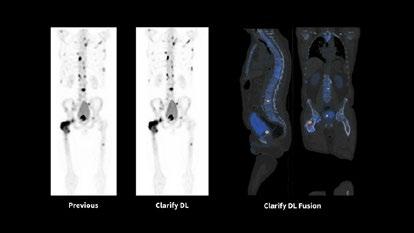

Issuu converts static files into: digital portfolios, online yearbooks, online catalogs, digital photo albums and more. Sign up and create your flipbook.